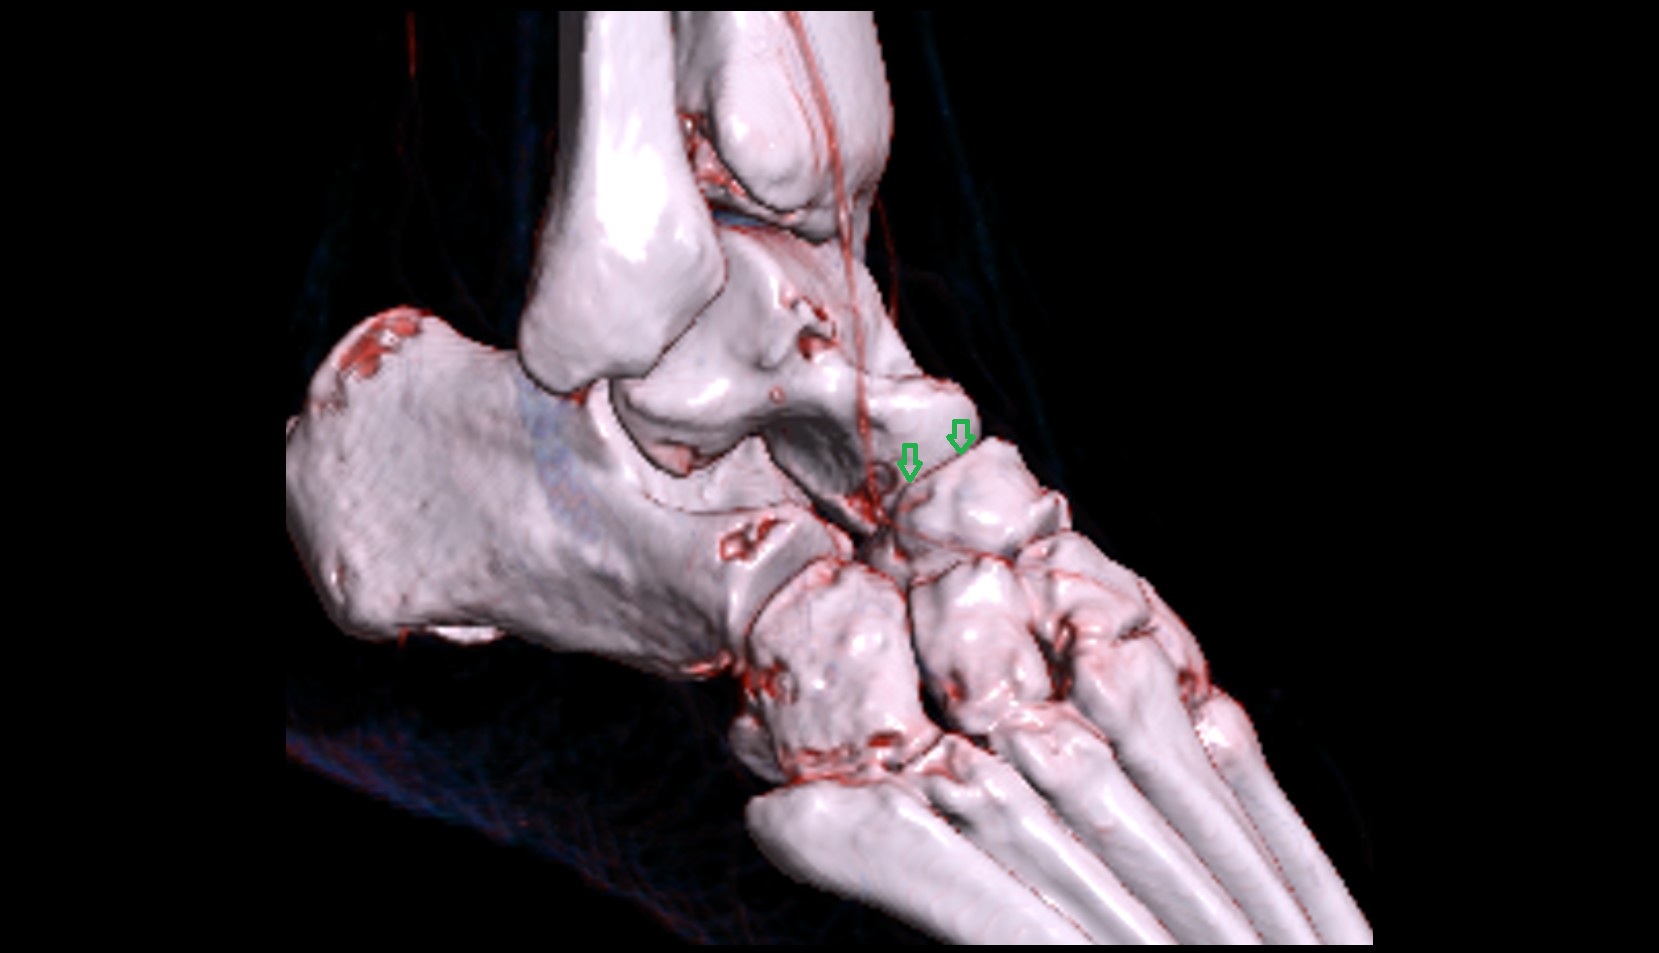

- Talus

- Head of talus

- Body of talus

- Neck of talus

- Calcaneus

- Cuboid

- Ankle joint

- Talocalcaneal joint

- Talocalcaneonavicular joint

- Calcaneocuboid joint